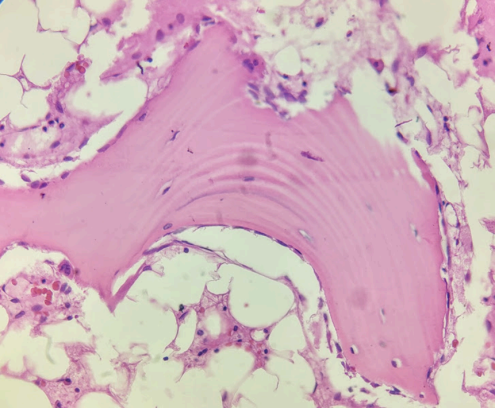

El estudio histológico evidenció osteomielitis crónica supurativa asociada a necrosis ósea. (Fig. 1 a 3)

Figura 3: Trabéculas óseas remodeladas.